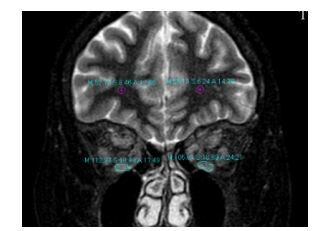

1.2.5 SIR值测量方法在STIR序列冠状位分别测量眼外肌T2值,多条眼外肌病变者,以信号最强者为代表。同时在冠状位选取距离眼眶后极约2 cm处测量同侧脑白质信号值(图 1),眼外肌最高信号值与脑白质比值即为SIR值。

|

图 1 眼外肌T2信号值及脑白质信号值 Figure 1 T2 values of the extraocular muscles and white matter. |